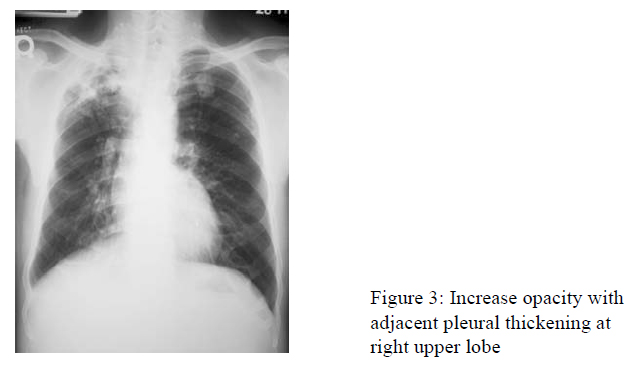

Complete blood counts were normal. Erythrocyte sedimentation rate 25 mm/hr. C-reactive protein less than 0.35 mg/dL. Urinalysis was normal. Serial chest radiographs showed parenchymal shadows over the right upper zone with some adjacent pleural thickening gradually worsening over a period of 1 month (Fig 3).